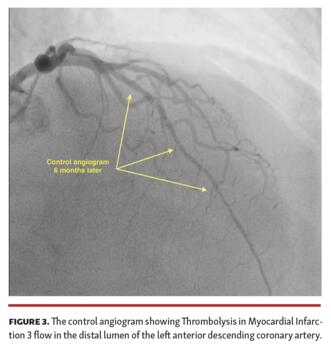

A 48-year-old male patient with a known diagnosis of hypertension presented after 6 months of chest pain (Canadian Cardiovascular Society II-III). Coronary angiography (CAG) showed a chronic total occlusion (CTO) of the left anterior descending (LAD) coronary artery from the mid-region (Figure 1 and Video Series). Percutaneous coronary intervention (PCI) was planned upon detection of viable tissue with myocardial perfusion scintigraphy. The distal portion of the CTO lesion was passed with microcatheter support and a hydrophilic wire. Distal flow could not be achieved despite successive predilations with small-diameter balloons (Figure 2). It was decided to implement an investment procedure to facilitate the next PCI process. Control angiogram 6 months later showed Thrombolysis in Myocardial Infarction (TIMI) 3 flow in the distal lumen of the LAD and there was no residual stenosis (Figure 3).

Subintimal plaque modification to restore some antegrade flow can promote subsequent lesion recanalization (investment procedure) in cases of failed re-entry into the distal true lumen during CTO-PCI. In this case, we aimed to present a case in which TIMI 0 flow was observed in the LAD after unsuccessful PCI attempt, but was left to recover with the investment procedure and TIMI 3 flow was detected in the control angiogram. In unsuccessful PCI-CTO cases, even in the presence of TIMI 0, flow can improve in the future through an investment procedure.